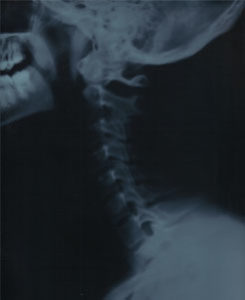

Cervical Spine

The cervical spine, consisting of the seven upper-most bones in the spine, begins at the base of the skull. There are several injuries and ailments that effect this area of the human body. These include.